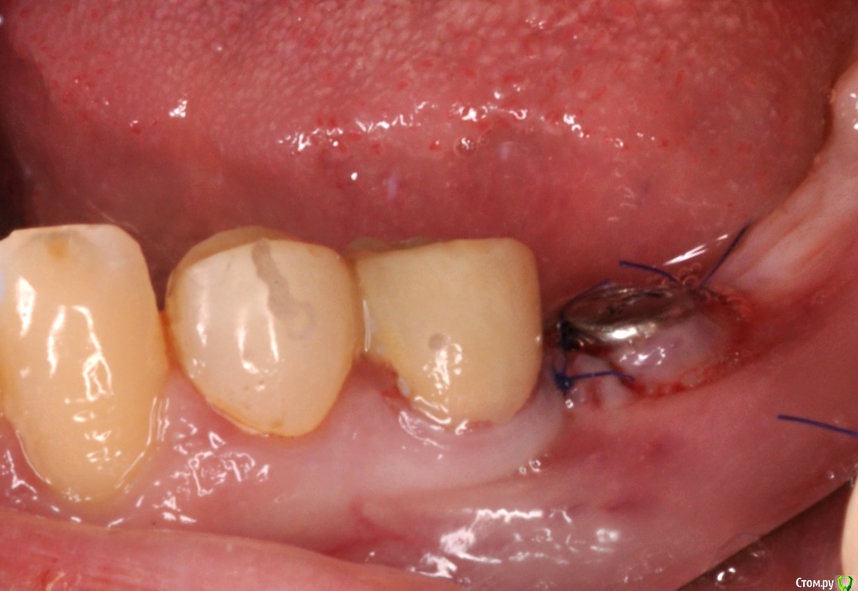

kriokov Опубликовано 7 сентября, 2016 Автор Поделиться Опубликовано 7 сентября, 2016 торк проверю - отпишусь торк 40, все штатно. Открывал без изысков. Крестально разрез, фдм, 2 шва унифлексом. Снимки свежие. 1 Ссылка на комментарий

kriokov Опубликовано 7 сентября, 2016 Автор Поделиться Опубликовано 7 сентября, 2016 (изменено) Без ССТ?да, там фдм стоит под 4мм, обьем мягкий есть, кератинизированная около 2 мм тоже есть. Решил сст не использовать. Заживет сфоткаю. Прсмотрим Изменено 7 сентября, 2016 пользователем kriokov 1 Ссылка на комментарий

kriokov Опубликовано 10 сентября, 2016 Автор Поделиться Опубликовано 10 сентября, 2016 Почему 2-й болт передумали ставить?ортопед с пациенткой решили, что короткого зубн ряда хватит Ссылка на комментарий